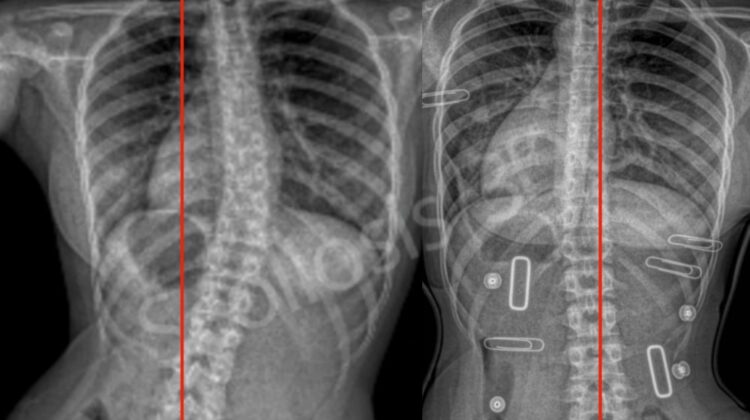

اعوجاج العمود الفقري هو انحناء غير طبيعي قد يكون على شكل حرف “C” أو “S”. غالبًا ما يظهر أثناء مرحلة النمو عند الأطفال والمراهقين.

يستخدم للأطفال والمراهقين الذين لا يزال لديهم نمو عظمي مستمر، لتقويم العمود الفقري ومنع زيادة الانحناء، وتحسين المظهر العام للظهر.

تثبيت الفقرات بالمسامير والقضبان المعدنية لإعادة استقامة العمود الفقري

أحيانًا دمج الفقرات للحفاظ على الثبات واستقرار العمود الفقري